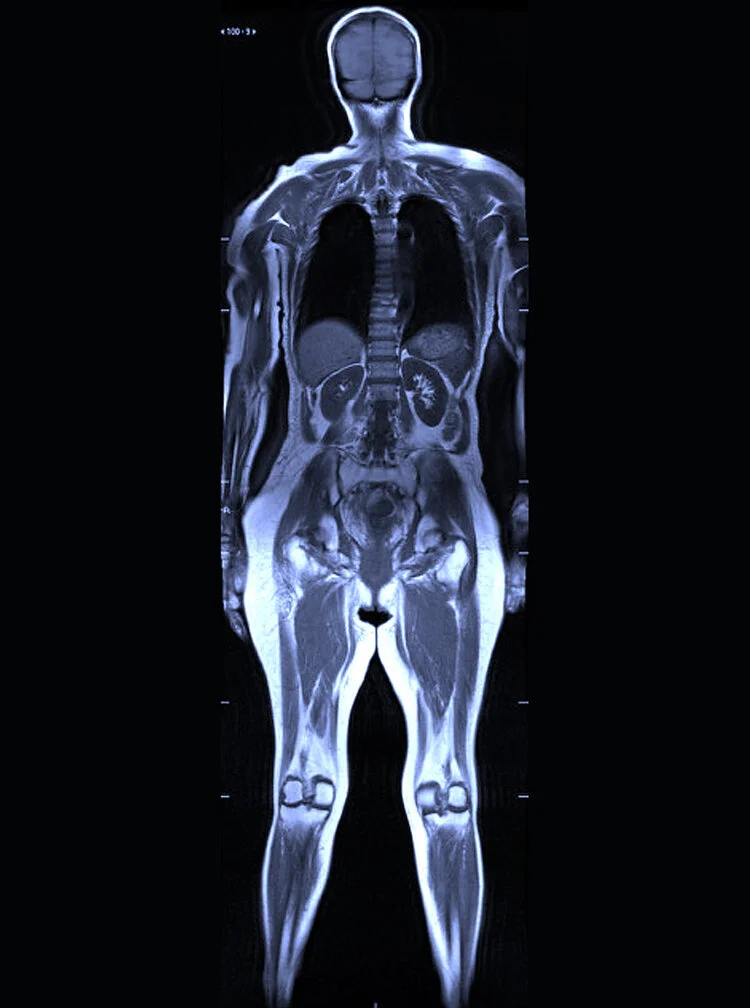

Diagnóstico integral del cuerpo humano

Realizamos estudios de imagen corporal con protocolos dirigidos que permiten evaluar órganos y sistemas de forma precisa, apoyando el diagnóstico, la estadificación y el seguimiento de diversas patologías.

Resonancia Magnética Corporal

Estudios multiparamétricos para diagnóstico oncológico y funcional.